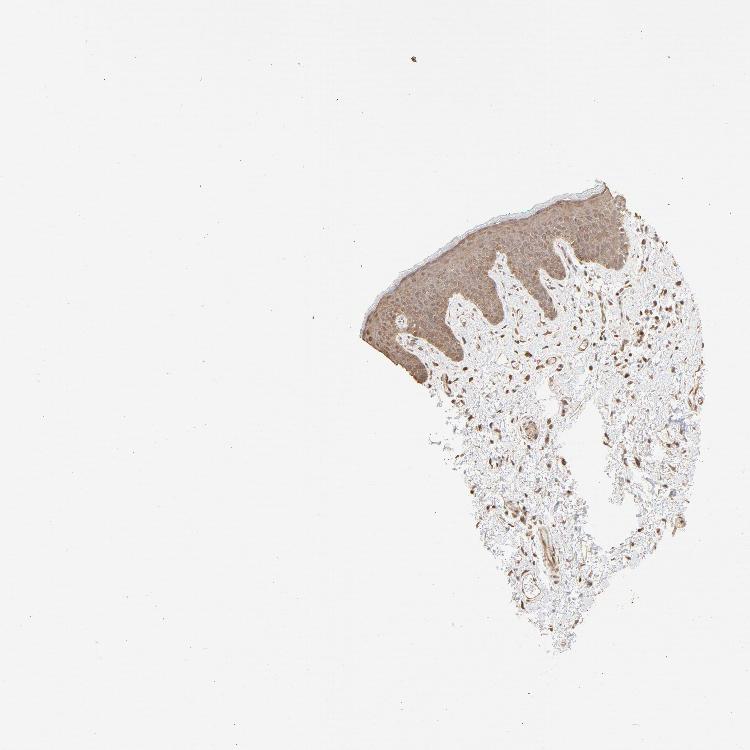

SKIN 2 - Antibody stainingi

Antibody staining in the annotated cell types in the current human tissue is reported as not detected, low, medium, or high, based on conventional immunohistochemistry profiling in selected tissues. This score is based on the combination of the staining intensity and fraction of stained cells.

Each image is clickable and will lead to virtual microscopy that enables deeper exploration of all samples and also displays staining intensity scores, fraction scores and subcellular localization as well as patient and tissue information for each sample.

Antibody HPA043236Antibody CAB003848

Epidermal cells MediumMedium